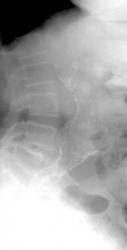

Radiography

Calcification of the abdominal aortic wall is frequently evident on plain radiographs of the abdomen, as demonstrated in the images below.